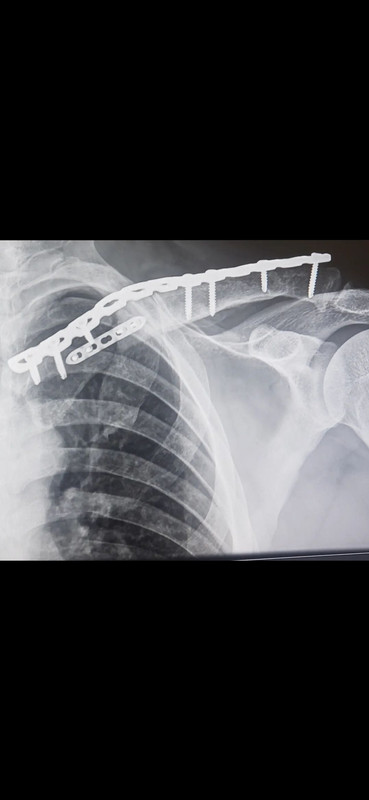

Did you end up with a plate and some screws? That's what I ended up with after a spill on my KLR. It's bothered me ever since.

multiple plates. Because after a month of UMR playing delay games they had to re-break it because it was healing AFU.